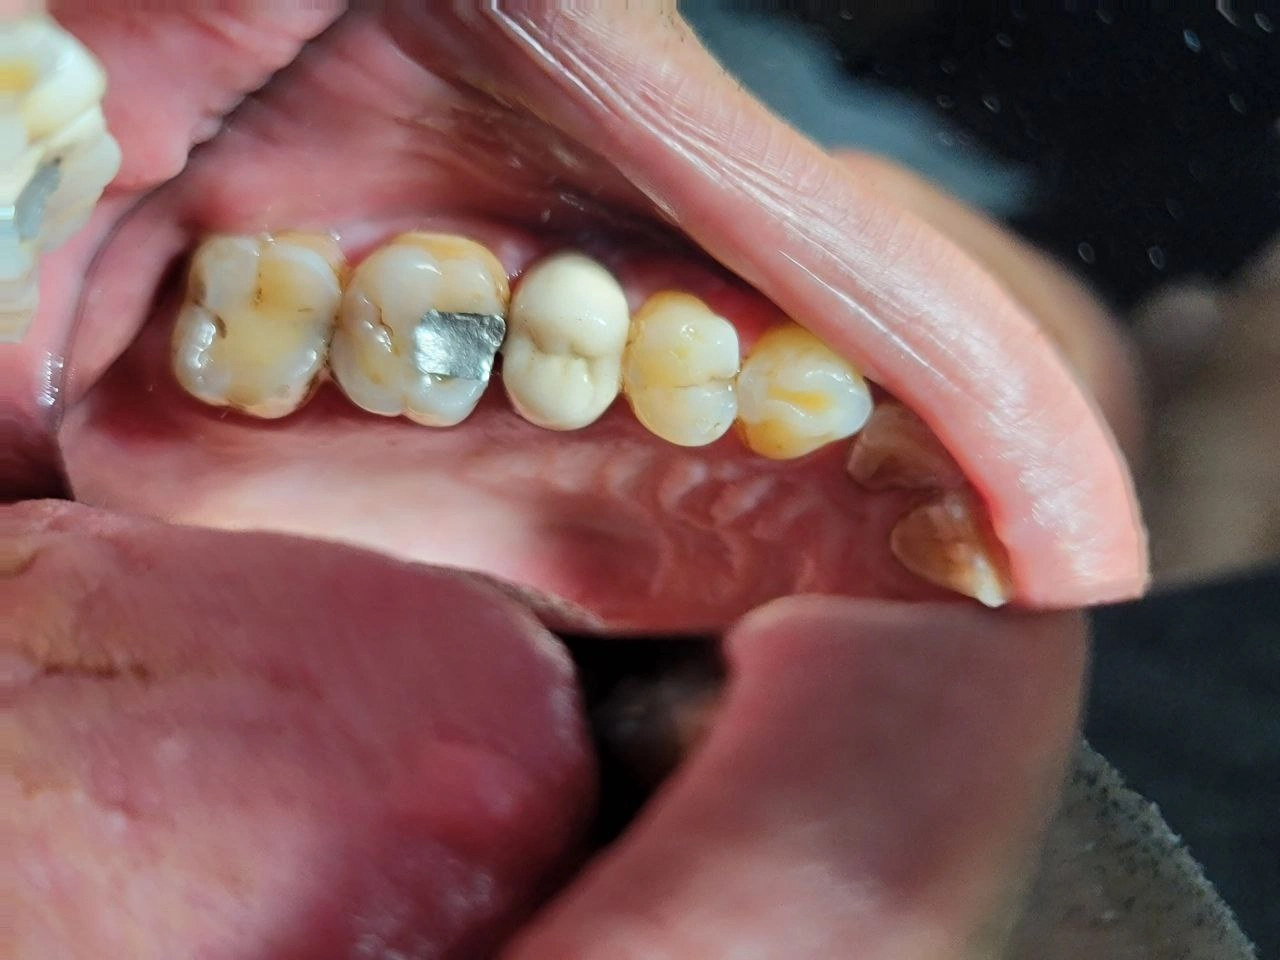

Clinical Cases